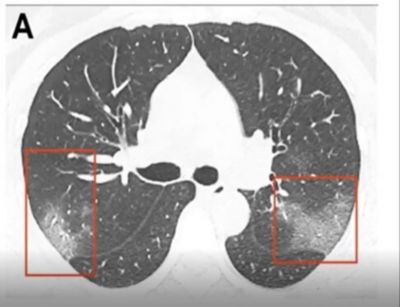

CT is still the gold standard for lung imaging, but it’s difficult to access a CT when you have a critical care patient. The volume of COVID patients, on top of limited access to CT machines, makes this method less than ideal for evaluating the lungs. Interestingly, in about 50 percent of patients, there are no findings between 0-2 days after the onset of symptoms of COVID. It takes about 3-5 days before CT findings are positive. When they are positive, they have bilateral peripheral and basal ground glass opacities (Figure B) in about 50-75 percent of patients. The distribution through the lungs is typically in the lower part of the lungs, but as the disease severity evolves, the CT findings can also be much more extensive.

Figure B. CT scan of a positive COVID-19 patient. The red squares highlight the bilateral peripheral and basal ground glass opacities.